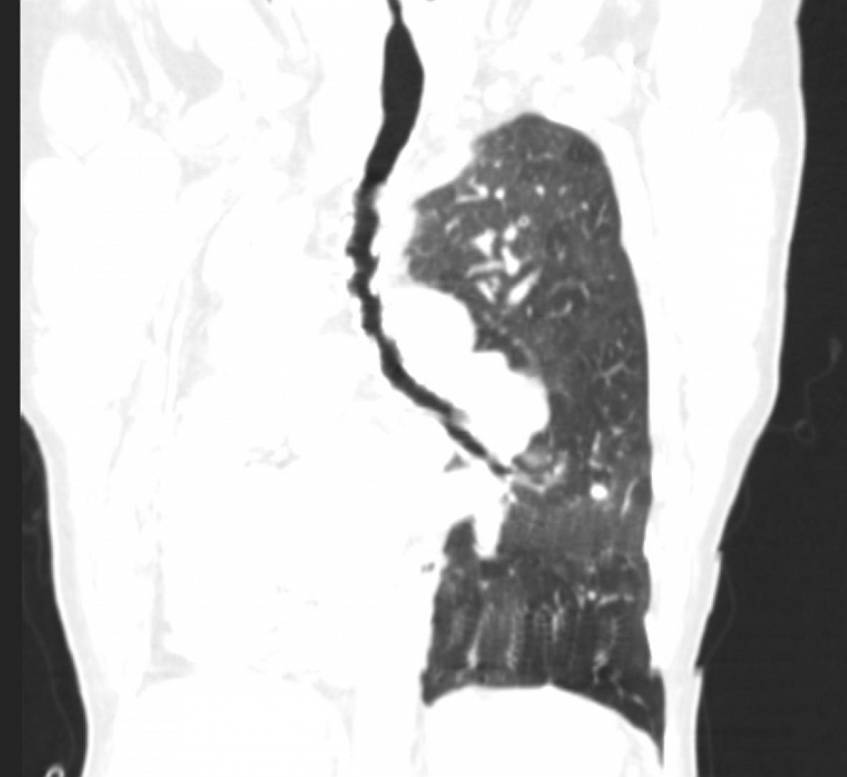

She underwent a CT scan, which showed a complete absence of the right lung, a normal hyperinflated left lung and a clear shift of the mediastinum to the right (dextrocardia). Absence of the right pulmonary artery and of the right main bronchus was also shown.

Imaging studies are essential for the diagnosis of pulmonary agenesis. The diagnosis is usually first suspected on chest radiography, which demonstrates a diffuse opacity of the affected hemithorax and an ipsilateral mediastinal shift [1, 6, 8]. A normal contralateral lung with compensatory hyperinflation and herniation across the midline is a common finding [6]. CT confirms the absence of lung parenchyma, pulmonary artery, and bronchial structures on the affected side [4, 6, 7]. CT angiography and MR angiography are currently the imaging modalities of choice in the diagnosis of this entity [6].